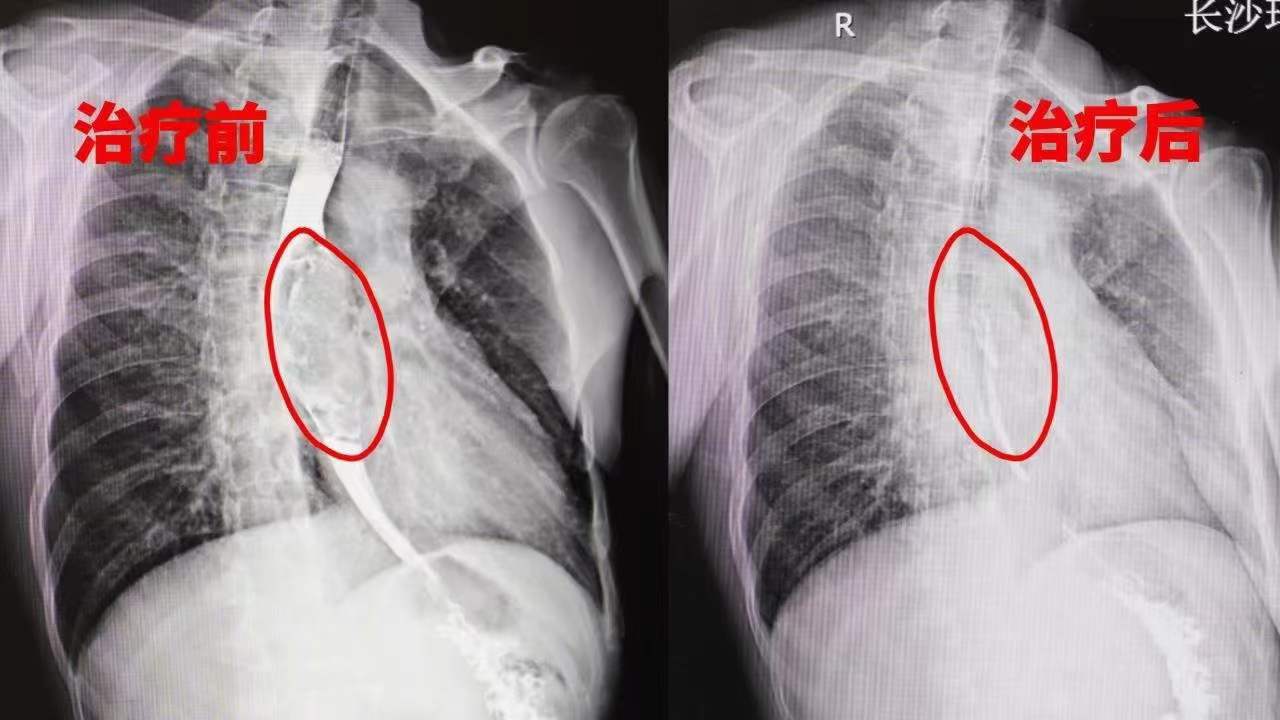

我们来看一个长沙肿瘤医院速锐智慧精确放疗的真实诊疗病例:51岁食管癌无法进食,经过速锐刀精确治疗2个月,肿瘤得到控制,进食恢复正常。长沙肿瘤医院速锐智慧精确放疗,吸引了来自全国各地的不远千里来到长沙寻求治疗。